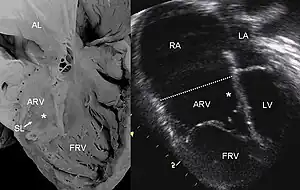

| Pathological specimen and ultrasound image of a heart with Ebstein's anomaly: Abbreviations: RA: right atrium; ARV: atrialized right ventricle; FRV: functional right ventricle; AL: anterior leaflet; SL: septal leaflet; LA: left atrium; LV: left ventricle; asterisk: grade II tethering of the tricuspid septal leaflet | |

The annulus of the valve is still in the normal position. The valve leaflets, however, are to a varying degree, attached to the walls and septum of the right ventricle. A subsequent "atrialization" of a portion of the morphologic right ventricle (which is then contiguous with the right atrium) is seen. This causes the right atrium to be large and the anatomic right ventricle to be small in size.

Typically, anatomic abnormalities of the tricuspid valve exist, with enlargement of the anterior leaflet of the valve. The other leaflets are described as being plastered to the endocardium. Tethering the underlying ventricular wall is the most common for the posterior and septal leaflets, and sail-like anterior leaflets may be tethered to the RV free wall also. About 50% of individuals with Ebstein's anomaly have an associated shunt between the right and left atria, either an atrial septal defect or a patent foramen ovale.[4]